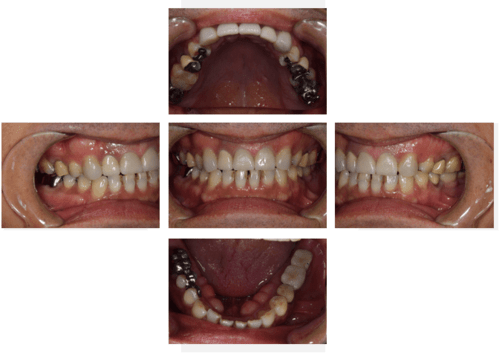

インプラント治療の症例7

口腔内写真-1

口腔内写真-2

- Before

- 途中経過

- After

| 年齢 | 40代・男性 |

| 主訴 | 主訴:インプラントがしたい 治療部位:左上5 |

| 治療内容 | インプラント埋入、GBR(骨造成) |

| 治療費 |

合計:726,000円 【内訳】 診断料:55,000円 埋入料:165,000円 GBR(骨造成):110,000円 サージカルガイド:55,000円 2次オペ:22,000円 仮歯:55,000円 上部構造(フルジルコニア):187,000円 IV:77,000円 (2024年4月現在) |

| 治療期間 | 1年3ヶ月 |

| 治療方針 | 骨が吸収され厚みが十分にないため、インプラント埋入と同時にGBR(骨造成)も行いました。 骨質は垂直的にはボリュームがありましたが、柔らかいため骨とインプラント体が結合するまでの待機期間を長めに設定しました。 |

| 特記事項 | 待機期間は2ヶ月~6ヶ月ほど待ち、インプラント体と骨が結合するのを待ちます。 結合できたことをレントゲンを撮影して確認します。 |

| 担当者所見 | 左上5は2017年の初診時から歯冠がないため抜歯を勧めましたが、ご本人の希望もあり、予後が悪いことも説明した上で被せ物を被せました。 2022年8月にその被せ物が外れ、虫歯にもなり、保存不可能だったため抜歯をしてインプラントを行いました。 |